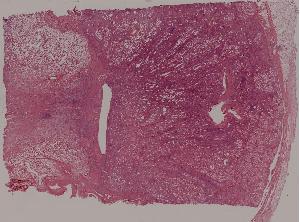

77.慢性肾盂肾炎